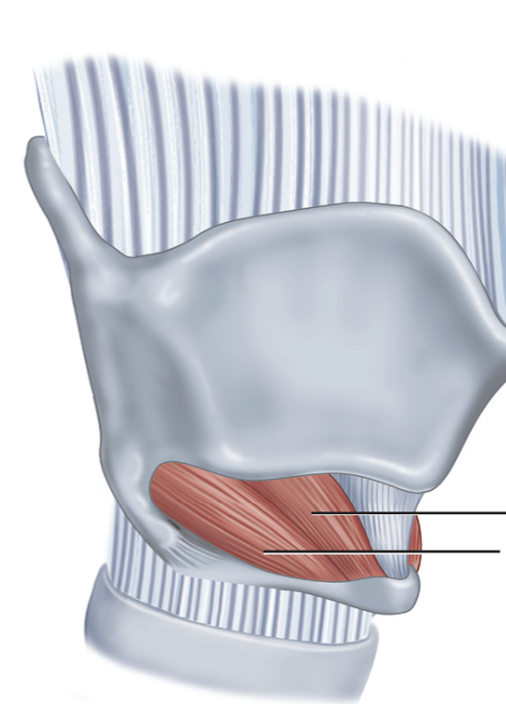

What is this muscle?

Lateral cricoarytenoid (LCA) (adduct VF)